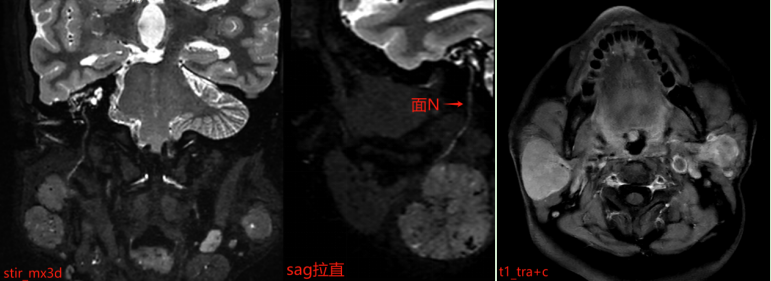

为什么影像检查中要「加扫」特殊序列

报告中特别提到「加扫 stir_mx3d 序列」,这一步骤非常重要。该序列能更清晰地显示病变与周围神经、血管的解剖关系。腮腺区域内走行着重要的面神经,它控制着我们的面部表情肌肉。如果手术中损伤该神经,可能导致术后面瘫,影响患者闭眼、微笑等基本功能。

3、评估关系:清晰显示病变与面神经、血管、下颌骨等重要结构的关系,为手术规划提供关键信息。